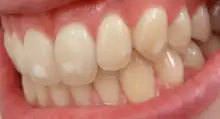

It appears as a range of visual changes in enamel[4] causing degrees of intrinsic tooth discoloration, and, in some cases, physical damage to the teeth. The severity of the condition is dependent on the dose, duration, and age of the individual during the exposure.[1] The "very mild" (and most common) form of fluorosis, is characterized by small, opaque, "paper white" areas scattered irregularly over the tooth, covering less than 25% of the tooth surface. In the "mild" form of the disease, these mottled patches can involve up to half of the surface area of the teeth. When fluorosis is moderate, all of the surfaces of the teeth are mottled and teeth may be ground down and brown stains frequently "disfigure" the teeth. Severe fluorosis is characterized by brown discoloration and discrete or confluent pitting; brown stains are widespread and teeth often present a corroded-looking appearance.[1]

The adequate diagnosis of fluorosis can be diagnosed by visual clinical examination. This requires inspection of dry and clean tooth surfaces under a good lighting.[6] There are individual variations in clinical fluorosis manifestation which are highly dependent on the duration, timing, and dosage of fluoride exposure.There are different classifications to diagnose the severity based on the appearances. The clinical manifestation of mild dental fluorosis is mostly characterised a snow flaking appearance that lack a clear border, opaque, white spots, narrow white lines following the perikymata or patches as the opacities may coalesce with an intact, hard and smooth enamel surface on most of the teeth.[7] With increasing severity, the subsurface enamel, all along the tooth becomes more porous. Enamel may appear yellow/ brown discolouration and/ or many and pitted white-brown lesions that look like cavities. They are often described as "mottled teeth".[8] Fluorosis does not cause discolouration to the enamel directly, as upon eruption into the mouth, affected permanent teeth are not discoloured yet. In dental enamel, fluorosis causes subsurface porosity or hypomineralizations, which extend toward the dentinal-enamel junction as the condition progresses and the affected teeth become more susceptible to staining. Due to diffusion of exogenous ions (e.g., iron and copper), stains develop into the increasingly and abnormally porous enamel.[7]